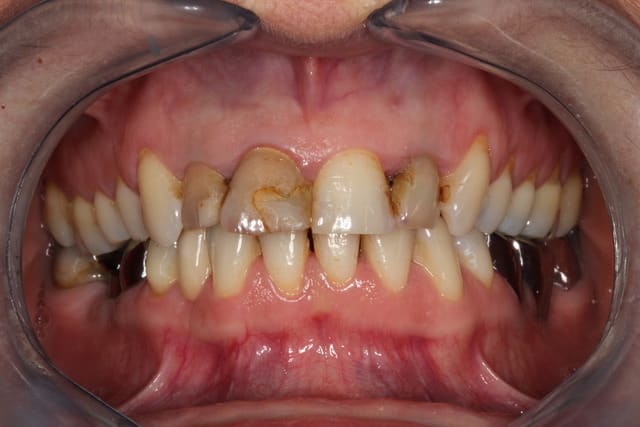

Voilà le plus près que j'aie en stock.

Oui la gencive est rouge, c'est un jeune qui m'a fait une GUNA.

Mais c'est que de l'iso 320 et 1/60.

Notez que les stries sur l'incisive, c'est naturel.

A posteriori, je constate que je n'étais pas dans le bon plan, c'est trop flou. j'avais séché les papilles, c'est pour dire si ça suintait....

Au final ce flash, pour ce que je fais avec me va très bien.